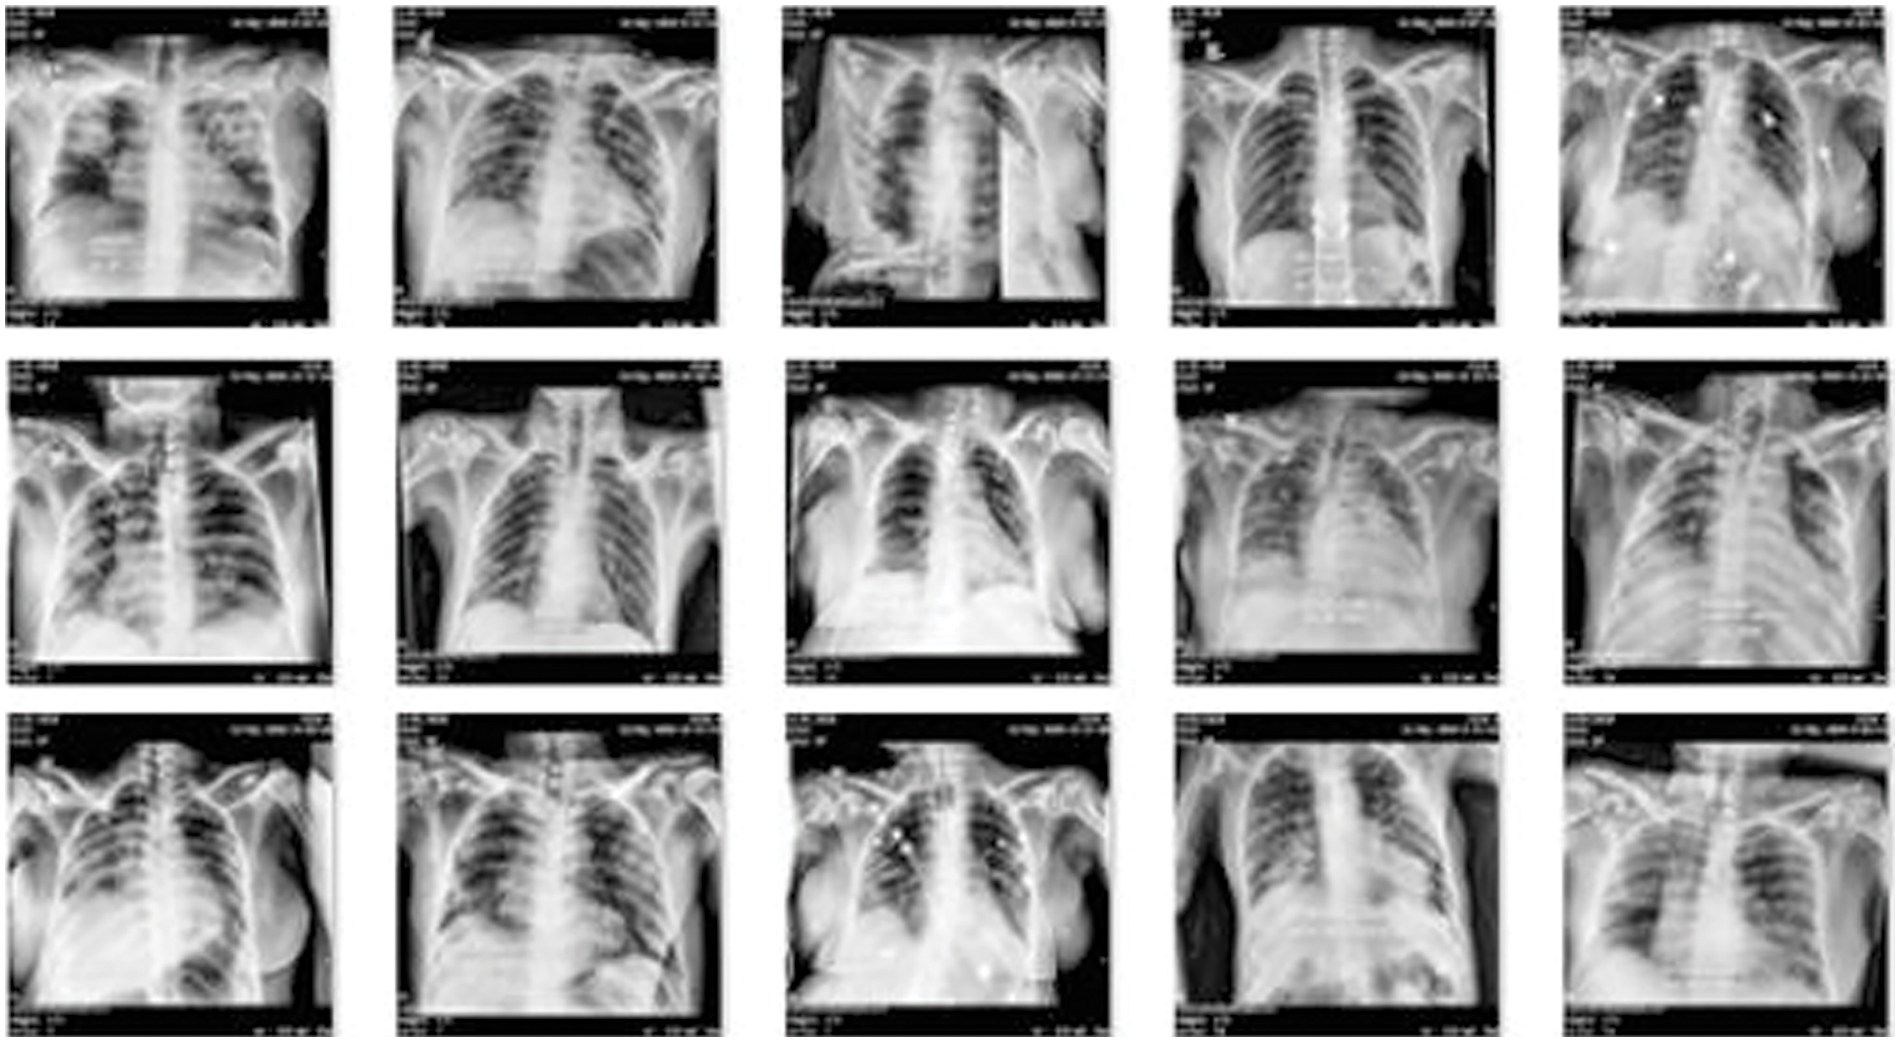

The first dataset, obtained from Kermany et al. [40], consists of normal and pneumonia cases. It encompasses CXIs of individuals without respiratory abnormalities as well as those diagnosed with pneumonia, including both bacterial and viral cases. The second dataset is a private dataset obtained from JPMC, for which proper permission was obtained which contains COVID-19 cases. This dataset contains CXIs of patients diagnosed with COVID-19, confirmed through RT-PCR tests. In Fig. 3, JPMC dataset example is given.

Figure 3: Example of COVID-19 dataset obtained from JPMC